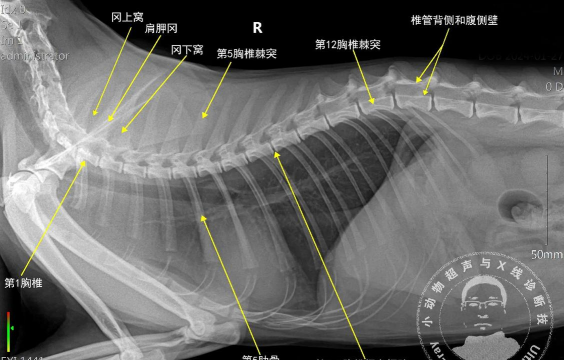

猫的脊柱和脊髓疾病

脊柱和脊髓疾病包括先天性缺陷、退行性疾病、炎症和传染病、肿瘤、营养性疾病、损伤和创伤、毒性疾病和血管疾病。